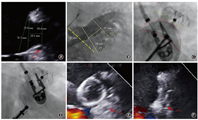

5.评估"PASS"原则(图4):Position(位置),器械最大直径平面正好或者稍远于并横跨左心耳开口;Anchor(锚定):通过牵拉确认封堵器固定好;Size(封堵器选型):封堵器实际展开最宽径相对于所选型号,应有一定的压缩;Sealing(封闭):保证所有的瓣叶都在器械远端并封闭,TEE测定封堵器残余分流≤ 5 mm[3,16]。

6.满足原则则释放封堵器。若不满足,则再回收以后重新定位释放,直至成功。(1) LAmbre封堵器评估"COST"原则:LCx:固定盘在LCx后面展开;Open(展开):固定盘充分展开,末端与连接在密封盘和固定盘之间的显影标志在一条直线上;Sealing(封闭):密封盘达到最佳封堵,TEE测定残余分流(peri-device leak, PDL) ≤ 3 mm[3,16];Tug test(牵拉):通过牵拉确认封堵器固定好(图5)。(2)ACP和Lacbes评估"CLOSE"原则:LCx:固定小叶展开后至少2/3要在LCx后面;Lobe(固定小叶):固定小叶要有一定压缩;Orientation(轴向):固定盘要与封堵器径线垂直;Separation(分离):固定盘和封堵盘要分离;Elliptical(椭圆形):封堵盘要有一定的形变(图6)。(3)Leftear评估"CODIS"原则:固定盘在LCx后面展开;固定盘充分展开(Open );封堵盘(Dish)要有一定的形变;通过牵拉确保固定牢靠(Insurance);密封盘达到最佳封堵(Sealing),TEE测定PDL ≤ 3 mm。

所有患者术前均行TEE、TTE检查,以除外左心房血栓,并测量左心耳数据、评估心功能和瓣膜情况。左心耳开口,定义解剖学开口[15],即左上肺静脉(left superior pulmonary vein,LSPV)嵴部与左回旋支(left circumflex,LCx)处连线(图1)。但2类封堵器测量稍有差别。使用PLO所测量的左心耳开口,位于连线内侧,等同于封堵器展开后最大直径平面所在位置的径线,而DLO所测量的为连线外口。左心耳深度,为开口线中点垂直线至内壁最深的径线。DLO需要测量封堵盘的锚定区(landing zone)直径,为平行开口线以内5~10 mm处的径线[6,15]。建议还需要参考LSPV嵴部至二尖瓣瓣环根部的距离,此为封堵盘最大直径。

TEE指导或X线指导下完成房间隔穿刺,穿刺点靠下最重要,其次是靠后。TEE同时在主动脉短轴切面和双房切面指导穿刺针向下及向后穿刺卵圆窝;X线指导下向下、稍向后穿刺(图3)。完成房间隔穿刺后,静脉推注普通肝素100 U/kg,后每隔1 h追加1 000 U。

完成房间隔穿刺后,若合并房颤消融,则先完成消融,再开始左心耳造影及封堵。左心耳造影及测量:一般采用右前斜(RAO)30°+足位(CAU)20 ° (相当于TEE 135 ° )、RAO 30 ° +头位(CRA)20°(相当于TEE 45°)及封堵器的"切线位"。